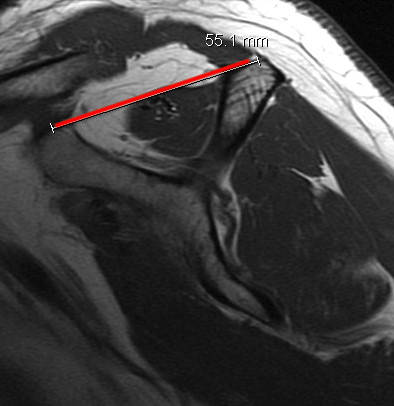

Measure tear in the coronal and sagittal plane

Small full thickness rotator cuff tear of supraspinatus - retracted to footprint

Large full thickness tear of supraspinatus and infraspinatus tendon - retracted to midhumeral head

Massive rotator cuff tear of the supraspinatus and infraspinatus tendon - retracted to glenoid